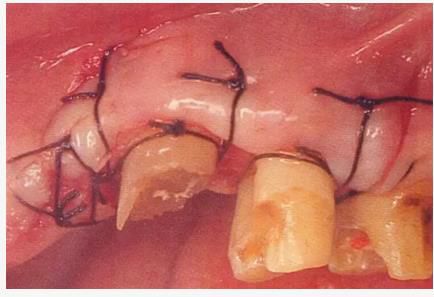

病例3 對于上頜前牙部的齦下齲壞,通過APF和FGG進行治療的病例

圖6-1

上頜前牙的牙頸部及齦下存在齲壞。

圖6-2 初診時的X光照片。齦下齲壞延伸到牙槽嵴頂,根管治療也不徹底。